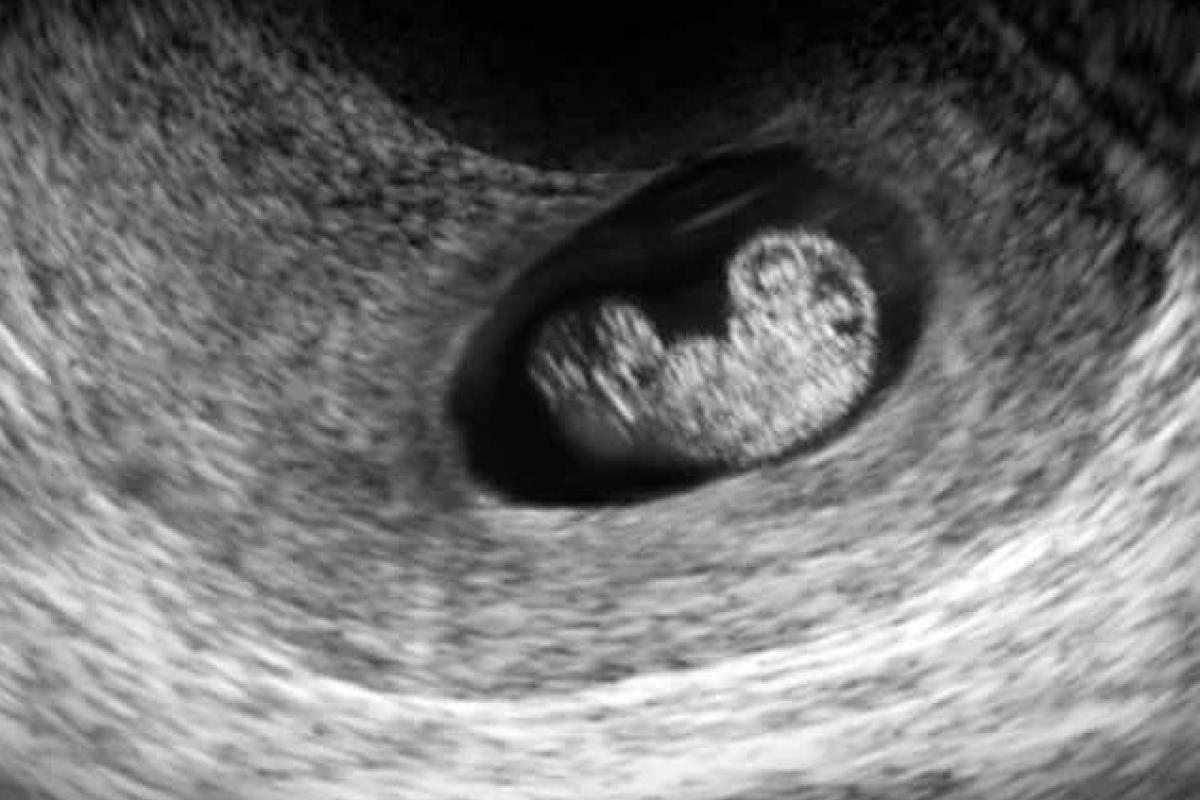

7 неделя беременности - это середина 2-го месяца. Вы уже можете начать ощущать характерные симптомы - тошноту и рвоту, хотя у многих женщин преобладают сонливость и утомляемость. Время для первого визита к гинекологу. Зародыш еще небольшой - около 4-5 мм, но быстро развивается.

7 неделя беременности - момент, когда голова ребенка развивается исключительно хорошо. Если бы вы могли посмотреть на него под микроскопом, вы бы увидели, что он уже имеет правильную форму и все больше и больше деталей.

пятна медленно превращаются в глазные яблоки, также можно увидеть дырочки, которые вскоре превратятся в ноздри. Также видны зачатки языка, рта и зубов. Руки и ноги значительно вырастают, а на их концах есть семена для рук и ног. Сердце разделено на правый и левый желудочки, и оно бьется четко и быстро - примерно в два раза быстрее вашего. У ребенка уже сформирован скелет, хотя пока он состоит только из мягких хрящей. Внутренние органы все еще развиваются, особенно пищеварительная система - кишечник и печень, но также и внутренние половые органы - у мальчика формируются пенис и яички, а у девочки - яичники. Хотя эти органы уже формируются, снаружи их не видно, поэтому на УЗИ определить пол ребенка не представляется возможным .